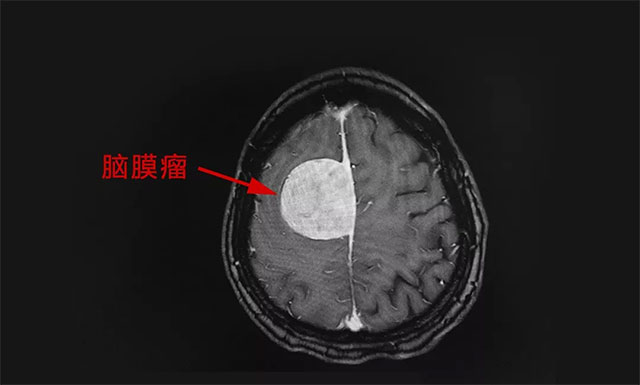

为完善其检查,郭女士做了头部 MRI 检查,结合其病史、病症及影像学结果,患者郭女士被诊断为:右侧额叶大脑凸面脑膜瘤,肿瘤大小约为 4.5cm x 4.4cm x 4.0cm ,如鸡蛋般大小。

▲ 标记处为脑膜瘤

潘仁龙主任表示,一般脑膜瘤在 2厘米以内是属于比较小的脑膜瘤,而这样大的脑膜瘤 (4.5cmx4.4cmx4.0cm) 还是比较少见的,由于肿瘤已经压迫到周围的脑神经和血管,同时又是在大脑功能区,已严重影响到患者走路及肢体的活动,加之其头痛厉害,手术指征明显,应尽早手术。